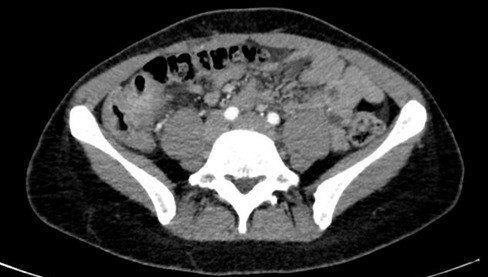

– une colite aiguë grave pouvant être inaugurale d’une maladie inflammatoire chronique de l’intestin (MICI). Ici, c’est un diagnostic possible car la patiente décrit des troubles digestifs évoluant depuis plusieurs années et elle fume, ce qui est un facteur de risque de développer une maladie de Crohn. Les critères de Truelove et Witts définissent la colite aiguë grave : > 6 selles sanglantes/24 h + protéine C réactive (CRP) > 30 mg/L ou hémoglobine < 10,5 g/dL ou température > 37,8 °C OU fréquence cardiaque > 90 bpm.